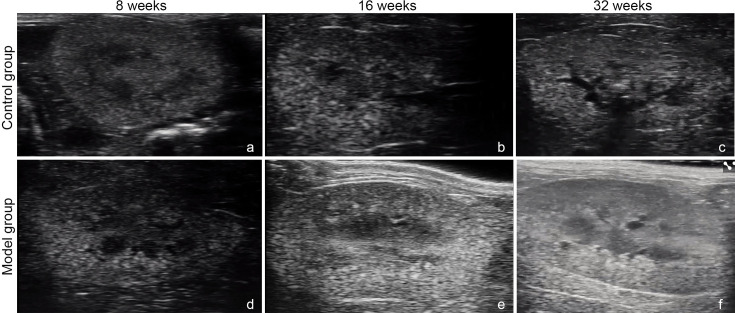

There are few ultrasonographic studies on the spontaneous type 2 diabetes mellitus db/db mouse. Our objective was to dynamically investigate and assess renal morphological and hemodynamic changes in spontaneous T2DM db/db mice through high-frequency ultrasound. Eighteen male db/db mice (the model group) and twelve male db/+ mice (the control group) were included. Body weight and fasting blood glucose were measured at the ages of 8, 16 and 32 weeks. High-frequency ultrasound examinations were conducted at the same ages. Compared with those in the control group, hematoxylin-eosin and Masson staining revealed pathological changes in the renal tissue of the db/db mice at 16 weeks of age, and the lesions were significantly aggravated at 32 weeks of age. The body mass of the mice in the model group increased significantly at 8, 16 and 32 weeks of age, and the kidney volume measured by ultrasound also increased with age. Compared with those of the control group, the blood flow scores determined via power Doppler were significantly different. The peak systolic velocity (PSV), end diastolic velocity (EDV), and resistive index (RI) of the renal artery and the PSV, EDV, and RI of the segmental artery were significantly different at the sixteenth week compared with those that at the eighth week. The results of high-frequency ultrasound revealed that the renal hemodynamics of db/db mice changed at the sixteenth weeks.